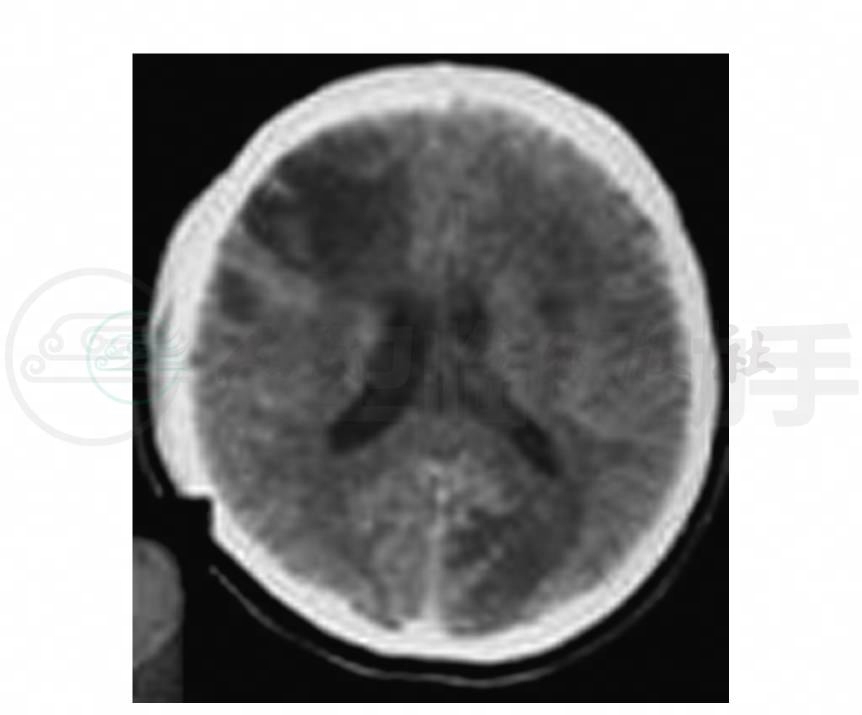

8.头颅CT(9月3日) 双额叶、左侧颞叶、枕叶、顶叶多发局限性低密度灶(图1),占位效应不明显,增强后无强化(图2),无囊变,无钙化,无结节,中线居中,脑室不大。

图1 头颅CT示双额叶、左侧颞叶、枕叶、顶叶多发局限性低密度灶

图2 头颅CT增强示病灶无强化